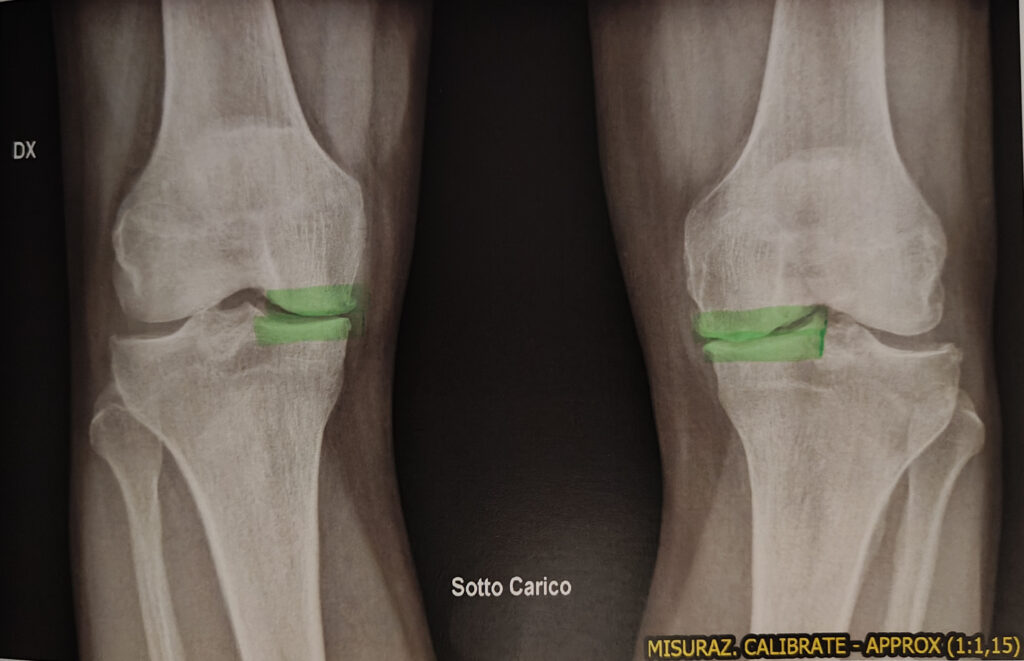

Spero che non sia una condizione irreversibile, sono arrivato a non avere più le cartilagini delle ginocchia e, forse per aver rimandato troppo un intervento, ora sono oggettivamente un invalido. Il chirurgo oggi mi ha detto: “ma con le ginocchia così ridotte non capisco come lei faccia a camminare!” Io lo capisco, non ne posso fare a meno, tutto qui.